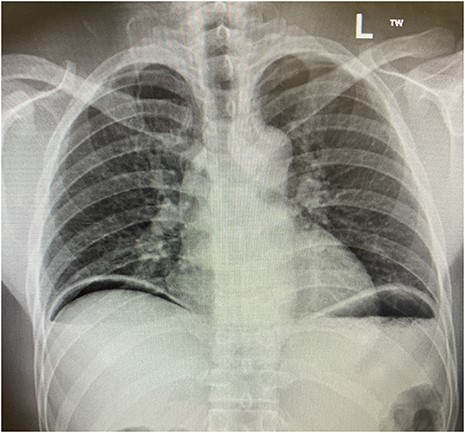

On examination in the emergency department, he was found to have localized peritonism to the epigastrium and was diaphoretic. An urgent erect chest radiograph (Figs 1 and 2) was revealing of gross pneumoperitoneum, presumably of a hollow viscous perforation as the source. General surgery was consulted after the presence of free air was detected. In the setting of the patient’s virgin abdomen and unremarkable surgical history, with peritonism and free intraperitoneal gas, the patient proceeded directly to urgent exploratory laparotomy with concurrent resuscitation measures, including intravenous fluid resuscitation and placement of an indwelling catheter.